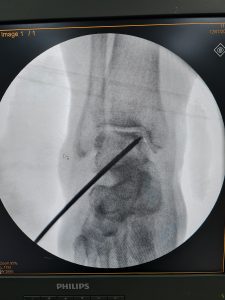

Ayak bileğinde talus kemiğinin beslenmesi özellik göstermekte ve eklem kıkırdağının beslenememesi nedeni ile kıkırdak hasarı hem sporcularda hem de travma nedeni ile birçok insanda görülebilmektedir. Bu olgularda da kemik iliği, kök hücre ve hücresele tedaviler yeni uygulamalardır.